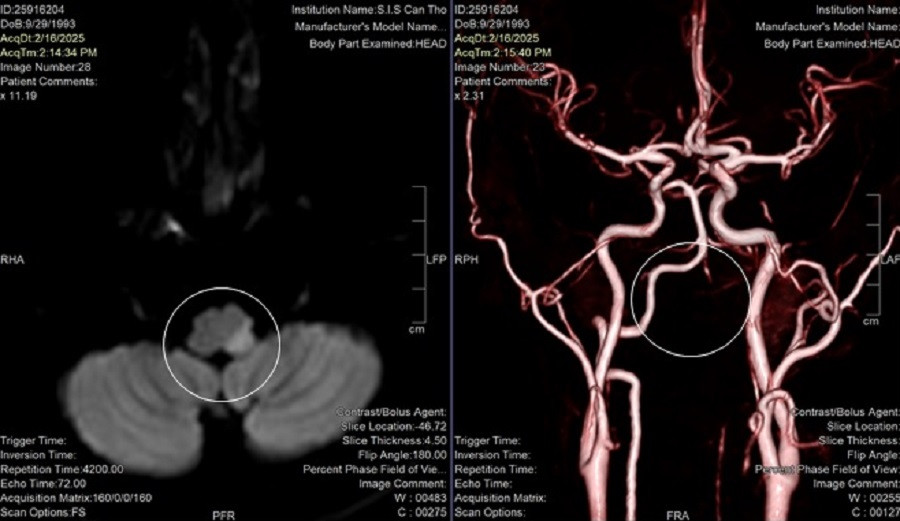

| Vị trí bị tắc động mạch đốt sống bên trái khiến người bệnh bị nhồi máu não |

Bệnh nhân được chỉ định chụp MRI khẩn cấp và làm các cận lâm sàng cần thiết truy tìm nguyên nhân. Theo BS.Trường, kết quả cận lâm sàng cho thấy, bệnh nhân bị hẹp nặng, gần tắc động mạch đốt sống bên trái gây nhồi máu não khu trú vùng thấp cầu não - hành não dẫn đến tình trạng mất khả năng nuốt hoàn toàn.